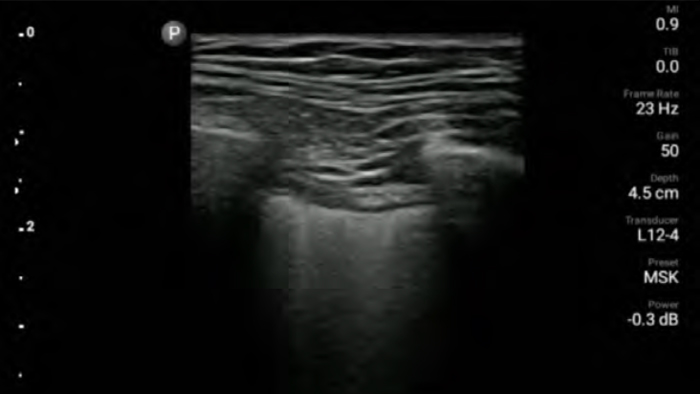

Lumify L12-4 broadband linear array transducer

• 12 to 4 MHz extended operating frequency range

• Aperture size: 34mm

• 2D, steerable color Doppler, M-mode, advancedXRES and multivariate harmonic imaging, SonoCT

• High resolution imaging for shallow applications: soft tissue, vascular, superficial, musculoskeletal and lung

• Center line marker

• USB-C transducer with replaceable cable